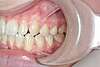

CAS ENFANT 1

Décalage des mâchoires et dents du haut très avancées

Patiente présentant un gros décalage entre les mâchoires du haut et du bas, avec les dents du haut très avancées.

Cas traité avec un appareil de correction des mâchoires, puis des bagues. Aucune opération chirurgicale n’a été réalisée.

Avant